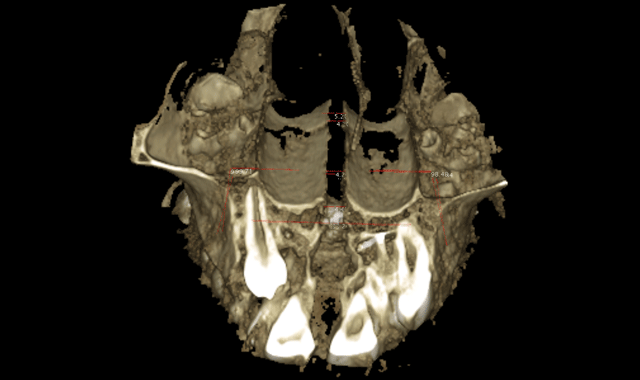

We can now extrapolate a coronal view that allows us to visualize many anatomical structures to formulate a diagnoses and treatment plan. The coronal view with a slice taken through the lingual roots of the maxillary first molars can be used to accurately determine the width of the maxilla and the inclinations of the maxillary molars (Fig. 5). We can then determine the mechanics needed for our patients in this dimension. The mechanics utilized on the patient in Figure 5 were expanded with skeletal fixation of the expander. No bands were attached to the molars.

Therefore, true horizontal expansion was achieved (Figs. 6a, 6b, 6c). These images were taken at the ULD settings on a Planmeca ProMax 3D Mid. Before placing stainless steel wires, many orthodontists will take a progress pan. to evaluate the roots of the teeth as far as proper bracket placements. This is an additional 35 microsieverts when using a traditional 2D panoramic machine. The ULD setting on the Planmeca Pro-Max 3D Mid machine with a limited field of view that only images the teeth is an effective dose of around 9 microsieverts.